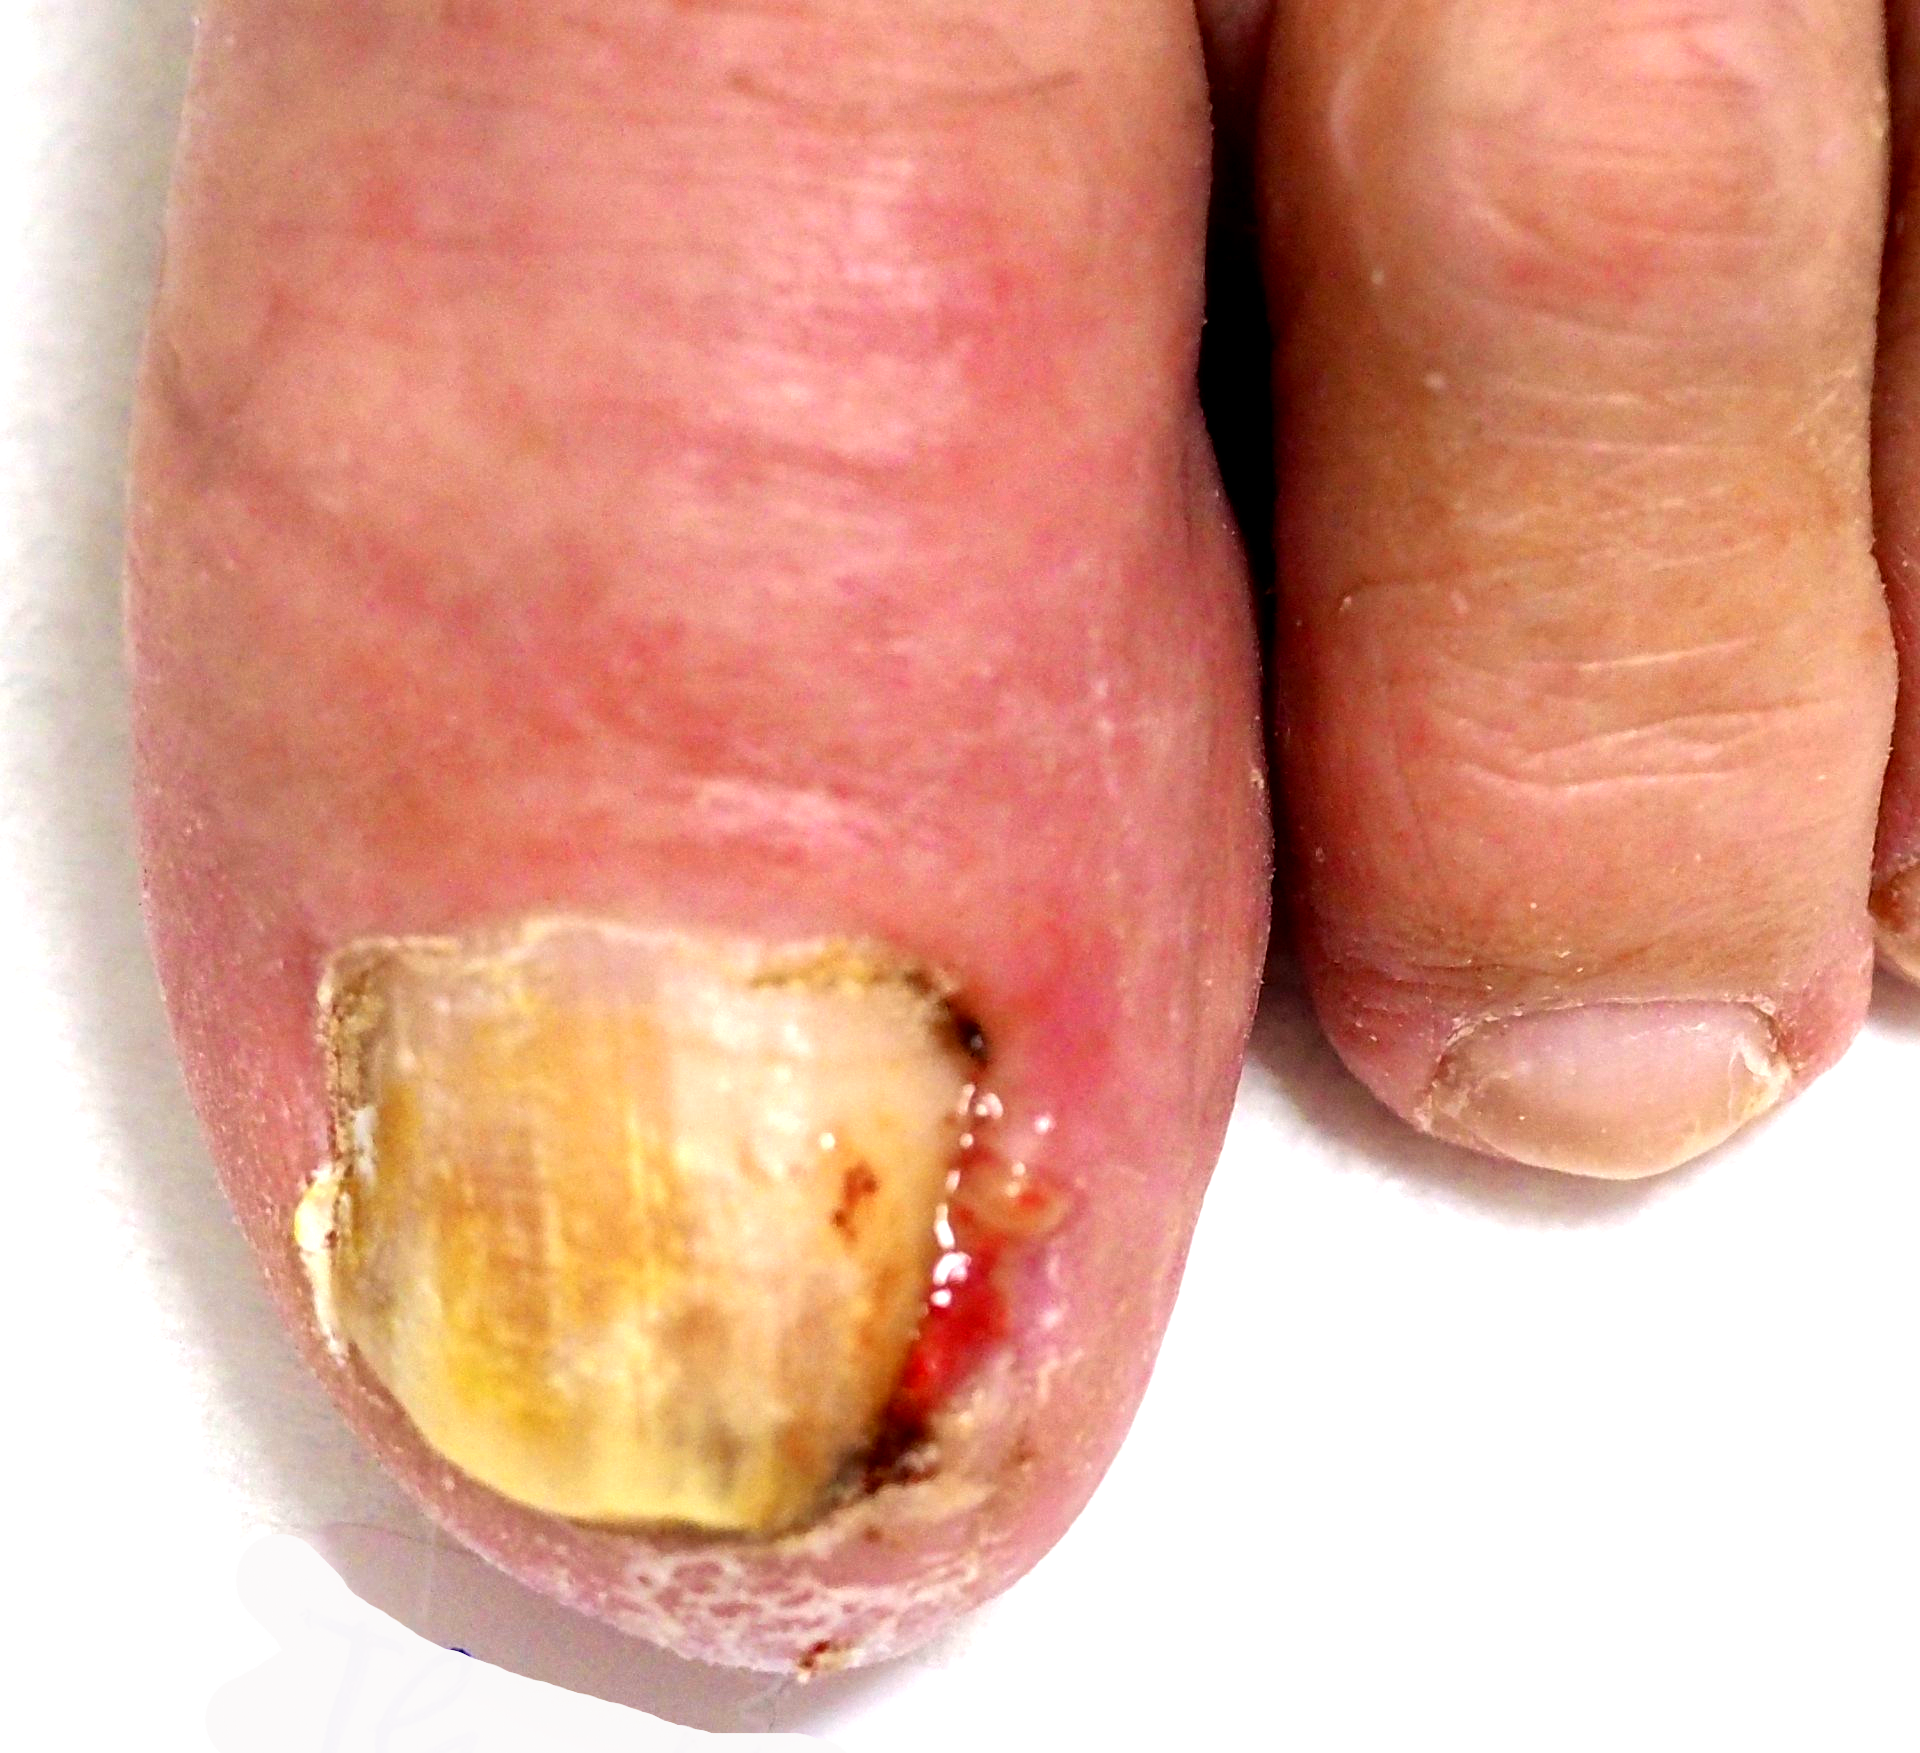

Hühnerauge subungual (unter der Nagelplatte)

Bild 1

die Ausgangssituation,

Bild 2

die geöffnete Nagelplatte unmittelbar nach der Entfernung des Hühnerauges